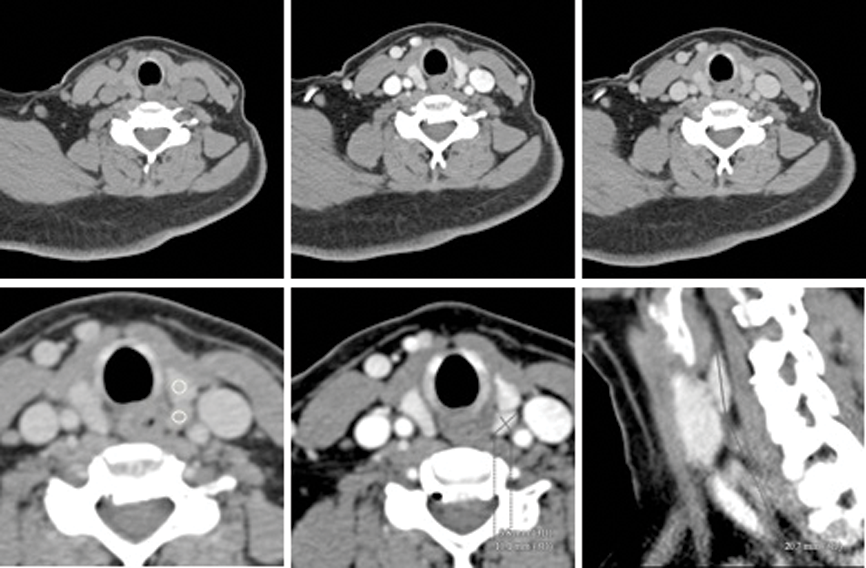

The parathyroid adenoma classically enhances vividly in the arterial phase with rapid subsequent washout (Figure 5). Furthermore, feeding vessels identified on the arterial images allow increased confidence in identification of adenomas [10]. Unenhanced images allow differentiation between parathyroid tissue and thyroid with the latter demonstrating higher density due to intrinsic iodine. As a first line investigation, 4D CT is highly accurate in adenoma location (87%) [10] and Rodgers et al. reported sensitivity of 70% in quadrant localisation versus 33% for sestamibi imaging and 29% for US [9].

Figure 5: 4D CT of the same patient as Figure 2. Non contrast image (top left) shows a lesion posterior to the left lobe of the thyroid which enhances avidly following contrast administration in the arterial phase (top middle) and shows rapid washout on delayed images (top right). Region of interest markers may be used on the delayed images (bottom left) to demonstrate more rapid contrast clearance in the lesion to measure the Hounsfield density in the lesion (100 HU) compared to the thyroid (130 HU). Axial and Sagittal reformats (bottom middle and right) demonstrate the size of the adenoma.